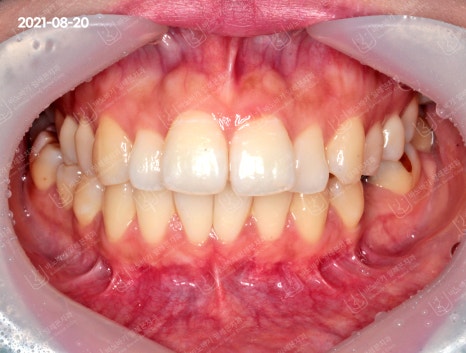

치아 사진을 촬영해보았는데요. 윗니와 아랫니가 생각보다는 깊이 물린 것 같진 않았습니다.

다만 상악 전치 4개의 배열이 불규칙한 것으로 나타났습니다. 하악 치열도 비뚤어져 있었고, 이로 인해 중심선이 어긋나서 불일치하는 경향을 보였습니다.